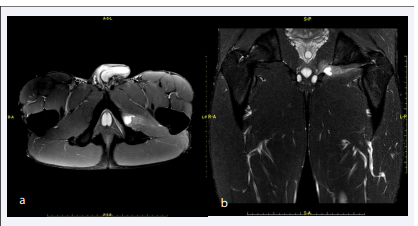

The last checkup was executed two weeks after the injury and demonstrated further reduction of the residual narrowing of diffusivity. In T2 acquisitions with fat suppression persisted hypersignal, lower than in previous investigations, involving only the obturator externus muscle. The signal alteration mainly affected the medial portion of the muscle. The hypersignal described at the obturator internus appeared completely resolved (Figure 3a).

Axial T2 (a) and coronal STIR TSE weighted (b) acquisitions  of the last MRI examination show minimal residual hypersignal only in  the medial portion of the muscle and significant reduction of bursitis.

Figure 3: Axial T2 (a) and coronal STIR TSE weighted (b) acquisitions of the last MRI examination show minimal residual hypersignal only in the medial portion of the muscle and significant reduction of bursitis.

Even the effusion described in previous investigation appeared considerably reduced, with an extension of just over 10 mm, with loss of the teardrop morphology previously described (Figure 3b). The scans obtained after intravenous infusion of paramagnetic contrast medium showed homogeneous contrast enhancement of the obturator internus muscle, in contrast with the markedly reduced signal in T2 acquisitions, expression of reparative colonization of the interstitial component between tertiary fibers of the muscle.